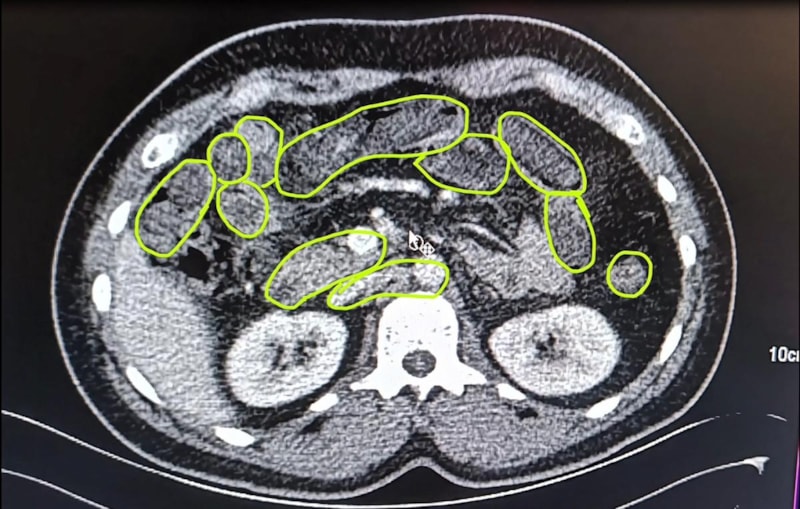

Zanlıların uyuşturucu maddeleri yutmuş olabileceğini değerlendiren ekipler bu kişileri hastaneye götürdü.

MİDELERİNDEN UYUŞTURUCU ÇIKTI

Röntgenlerinde midelerinde uyuşturucu madde olduğu belirlenen zanlılardan 20 gram çeşitli uyuşturucu madde ile 117 uyuşturucu hap ele geçirildi.